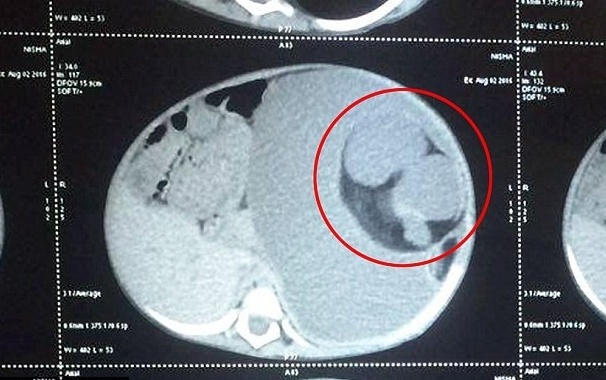

ومن بعدها لاحظ والدا الطفلة البالغة من العمر 15 شهراً، أنّ هناك ورماً كبيراً في معدتها فنقلاها إلى مستشفى لانكا غاناباثي كريشنا الهنديّة، فوجد الأطباء كتلة وزنها 3.5 كيلوغرمات من العظام، اللحم والشعر داخل بطن الطفلة.

وتم تشخيص إصابتها بمتلازمة "جنين داخل جنين"، وهي حالة نادرة أصابت 200 شخص في العالم على مرّ السنين.

وأكدى الموقع انه ام إجراء عملية جراحية معقّدة استمرت ساعتين، لإستئصال الحمل الذي ينمو في داخل معدتها.